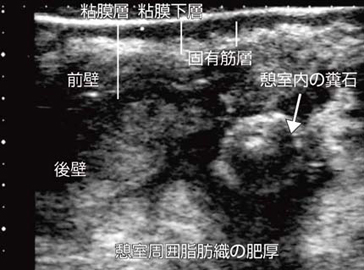

図11は,上行結腸憩室炎の縦断像である。壁の浮腫性肥厚,憩室および糞石とともに,周囲脂肪織の肥厚が描出されている。憩室炎や異物穿孔などの場合は,壁そのものの変化より周囲の変化を評価することが診断上重要である。

![]() 図11 上行結腸憩室炎の縦断像 |